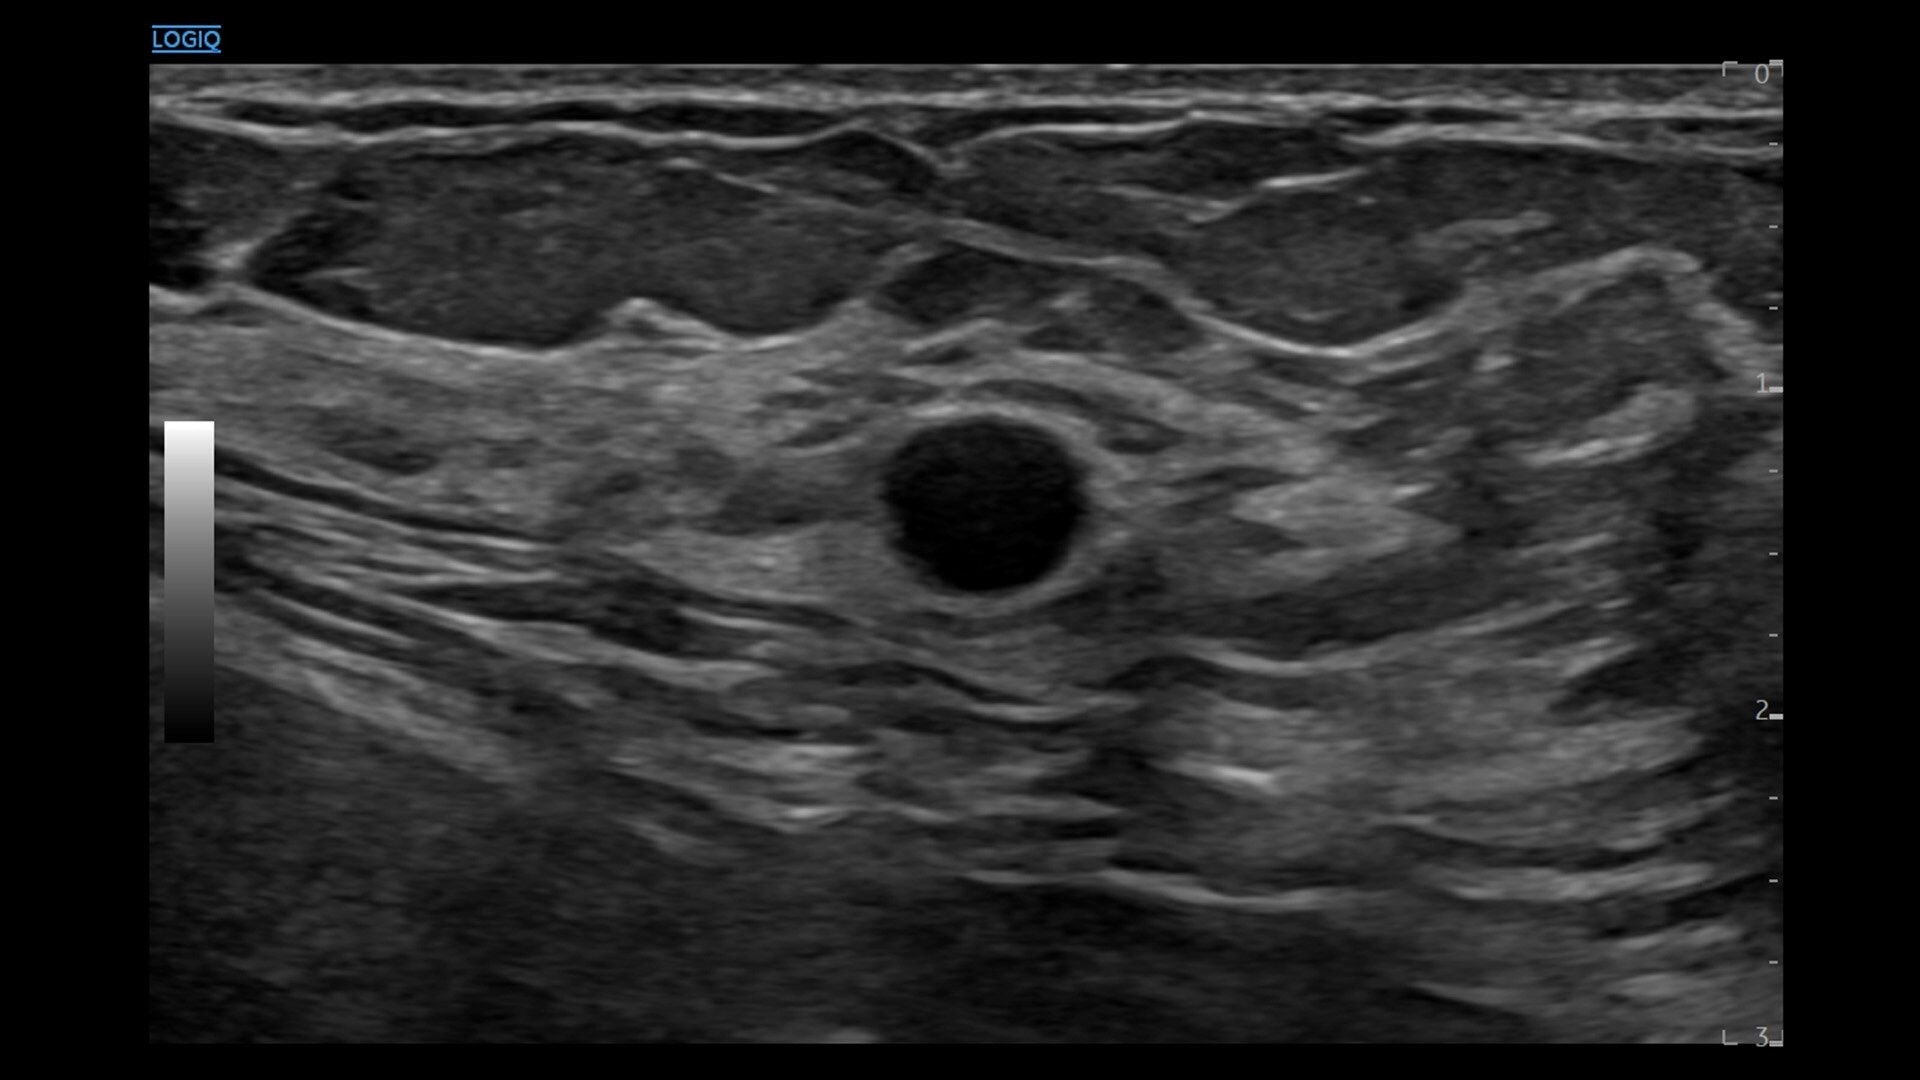

• cSound™ Architecture delivers exceptional clarity and resolution from near field to depth—with all pixels in focus

• Advanced flow modes give you the flexibility, from large vessels to fine microvascular detail, to visualize blood flow with precision